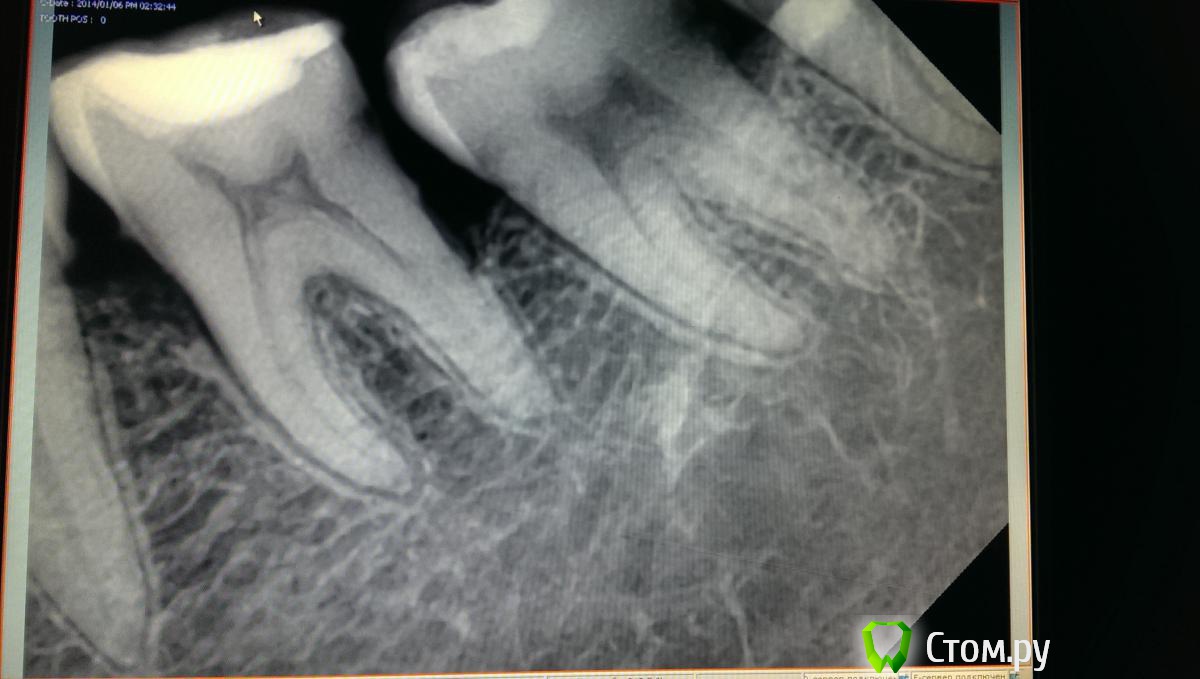

art700 Опубликовано 16 января, 2014 Поделиться Опубликовано 16 января, 2014 Вобщем спрошу здесь, дабы не создавать новой темы. Пациентка - ассистенка клиники, попала ко мне уже после одного доктора терапевта, решил посмотреть ее, ибо боли как говорят. Зуб 36 мучает, изначально беспокоила боль при чистки, запах ну и т.д. Как я понял для начала решили убрать плотный контакт с зубом 3.7, стало легче, но через пару дней появилась сильная боль на холодное, только на холодное причем. Думаю депульпировать уж или есть варианты какие? Снимок практически двухнедельной давности, сейчас по ее словам должно быть тоже самое, т.к практически ничего не делали, но фиг его знает. Вобщем болит. Ссылка на комментарий

Л Ю С Я Опубликовано 17 января, 2014 Поделиться Опубликовано 17 января, 2014 Вобщем спрошу здесь, дабы не создавать новой темы. Пациентка - ассистенка клиники, попала ко мне уже после одного доктора терапевта, решил посмотреть ее, ибо боли как говорят. Зуб 36 мучает, изначально беспокоила боль при чистки, запах ну и т.д. Как я понял для начала решили убрать плотный контакт с зубом 3.7, стало легче, но через пару дней появилась сильная боль на холодное, только на холодное причем. Думаю депульпировать уж или есть варианты какие? Снимок практически двухнедельной давности, сейчас по ее словам должно быть тоже самое, т.к практически ничего не делали, но фиг его знает. Вобщем болит.В чем причина деформации зубного ряда? Есть ОПТГ? Ну депульпируете, но резорбция то будет прогрессировать если не убрать причину. Антагониста у 6 наверное нет? Смотрите какой карман сформировался. Как там с гигиеной? Вобщем, смотрите в полость рта. Ссылка на комментарий